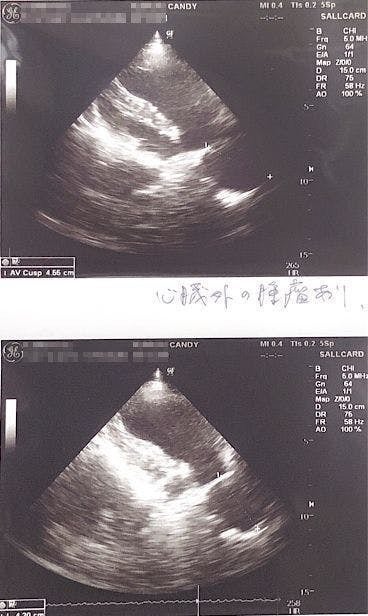

エコーを撮ったところ、体の中心に腫瘍の影があるのが見えると言われました。

「腫瘍が心臓を圧迫していて左の肺を押しつぶしている為(右肺のみの呼吸)、通常の半分の呼吸しか出来ていず、少し歩くだけでもすぐに苦しくなる状態です。」

とのことでした。